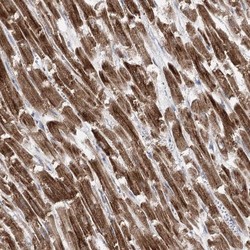

- Immunohistochemistry-Paraffin: Pyruvate Dehydrogenase E1 beta subunit Antibody [NBP1-87421] - Staining of human heart muscle shows strong cytoplasmic positivity in cardiomyocytes.